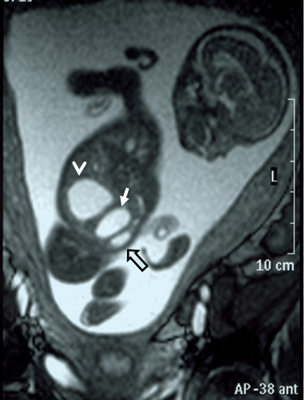

A 26-year-old pregnant women, gravida 1, para 0, was admitted to our prenatal diagnosis centre for detailed ultrasonography examination. Obstetric history was unremarkable. A single fetus was detected at 26 gestational weeks. A presacral located cystic mass measuring 45 × 55 × 40 mm was seen on ultrasound examination (Fig. 1). On doppler ultrasound, the cystic structure with both umbilical arteries around was considered an enlarged distally obstructed fetal bladder initially (Fig. 2). However, the bladder was later identified more superiorly. The amniotic fluid index was 129mm. Diagnosis of the cystic mass was unclear and a fetal MRI was performed, which delineated a large cystic mass with minimal internal echogenicity area, the type IV teratoma (big arrow head). The white arrow demonstrates a cystic mass considered as a hydrometrocolposis (Fig. 3).

In the axial plane, besides type IV SCT (big arrow head) and hydrometrocolpos (white arrow); both kidneys (white asterix) appeared in normal loca¬tion and anatomy (Fig. 4). In the coronal plane fetal bladder (black empty arrow) was noticed (Fig. 5).

Figure 3: Fetal MRI showing type IV teratoma (big arrow head) and the white arrow demonstrates hydrometrocolpos. |

Figure 4: Fetal MRI axial plane. |